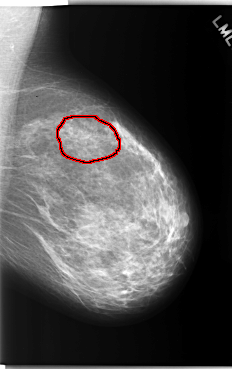

C_0207_1.LEFT_MLO

LEFT_MLO LINES 5904 PIXELS_PER_LINE 3704 BITS_PER_PIXEL 12 RESOLUTION 50 OVERLAY

FILE: C_0207_1.LEFT_MLO.OVERLAY

TOTAL_ABNORMALITIES 1

ABNORMALITY 1

LESION_TYPE CALCIFICATION TYPE PLEOMORPHIC DISTRIBUTION CLUSTERED

LESION_TYPE MASS SHAPE IRREGULAR MARGINS ILL_DEFINED

ASSESSMENT 4

SUBTLETY 3

PATHOLOGY MALIGNANT

TOTAL_OUTLINES 1

BOUNDARY